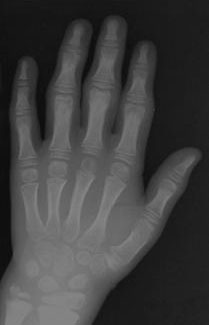

c) Juntas Pequenas: Embora as alterações na mão apareçam cedo, envolvimento de pequenas articulações parece ser menos incapacitante do que os efeitos em grandes articulações.

Há inchaço proeminente das articulações interfalangeanas, mas muitas vezes com pouca dor. No entanto, a rigidez pode causar dificuldades motoras finas e funcionais.